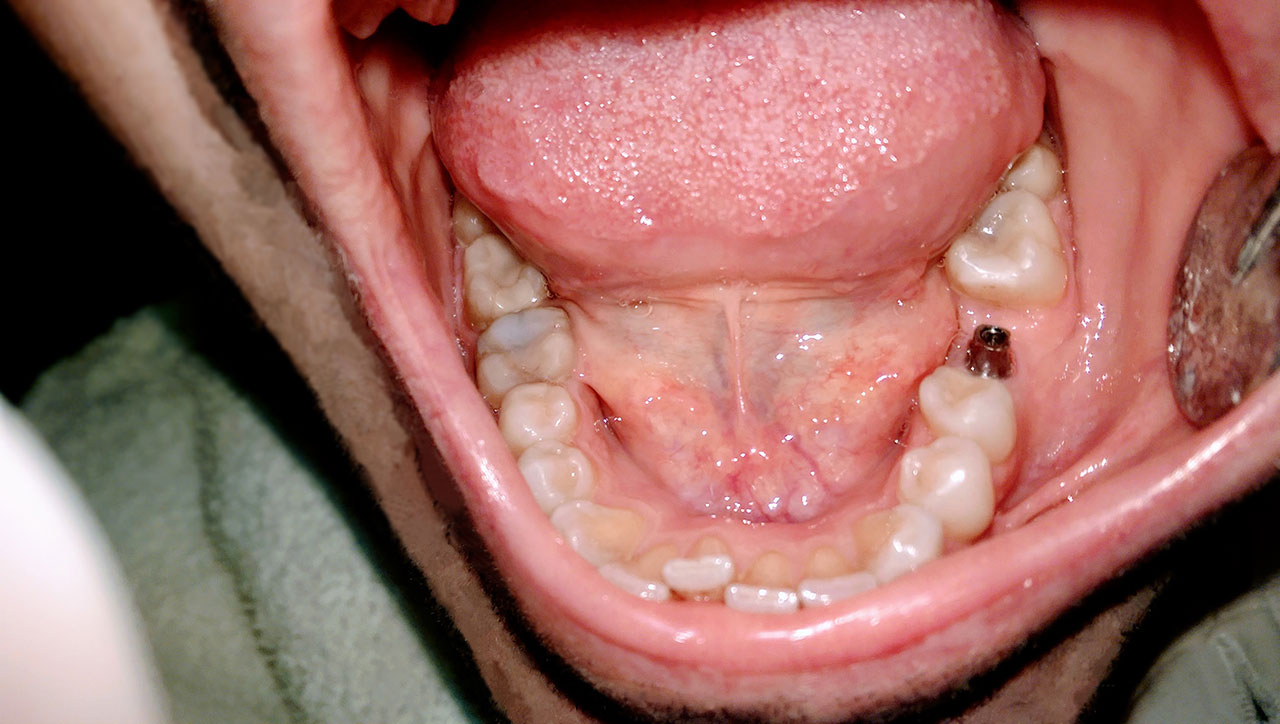

Alsó állcsont teljes rehabilitációja 72 óra alatt

Alsó állcsont teljes rehabilitációja 72 óra alatt, azonnal terhelhető implantátumokkal súlyos paradontitisben szenvedő dohányzó páciens esetében. Az alsó állcsont fogai mind mozogtak az előrehaladott fogágypusztulás miatt.

A fogakat eltávolítottuk, a gyulladt, fertőzött csontot kitakarítottuk, kifertőtlenítettük, majd azonnal implantáltunk.

Svájci, IHDE márkájú, azonnal terhelhető implantátumokat helyzetünk be, és ezekre harmadnapra rögzített, hosszútávú, fémvázas, esztétikus műanyaggal leplezett hidat ragasztottunk be.

Ezt az ideiglenes hidat a sebek gyógyulása miatt használjuk, de tartóssága miatt véglegesként is használható. A legtöbb esetben, ahogy itt is, 6 hónap múlva porcelán hídra cseréljük, a teljes gyógyulás után.